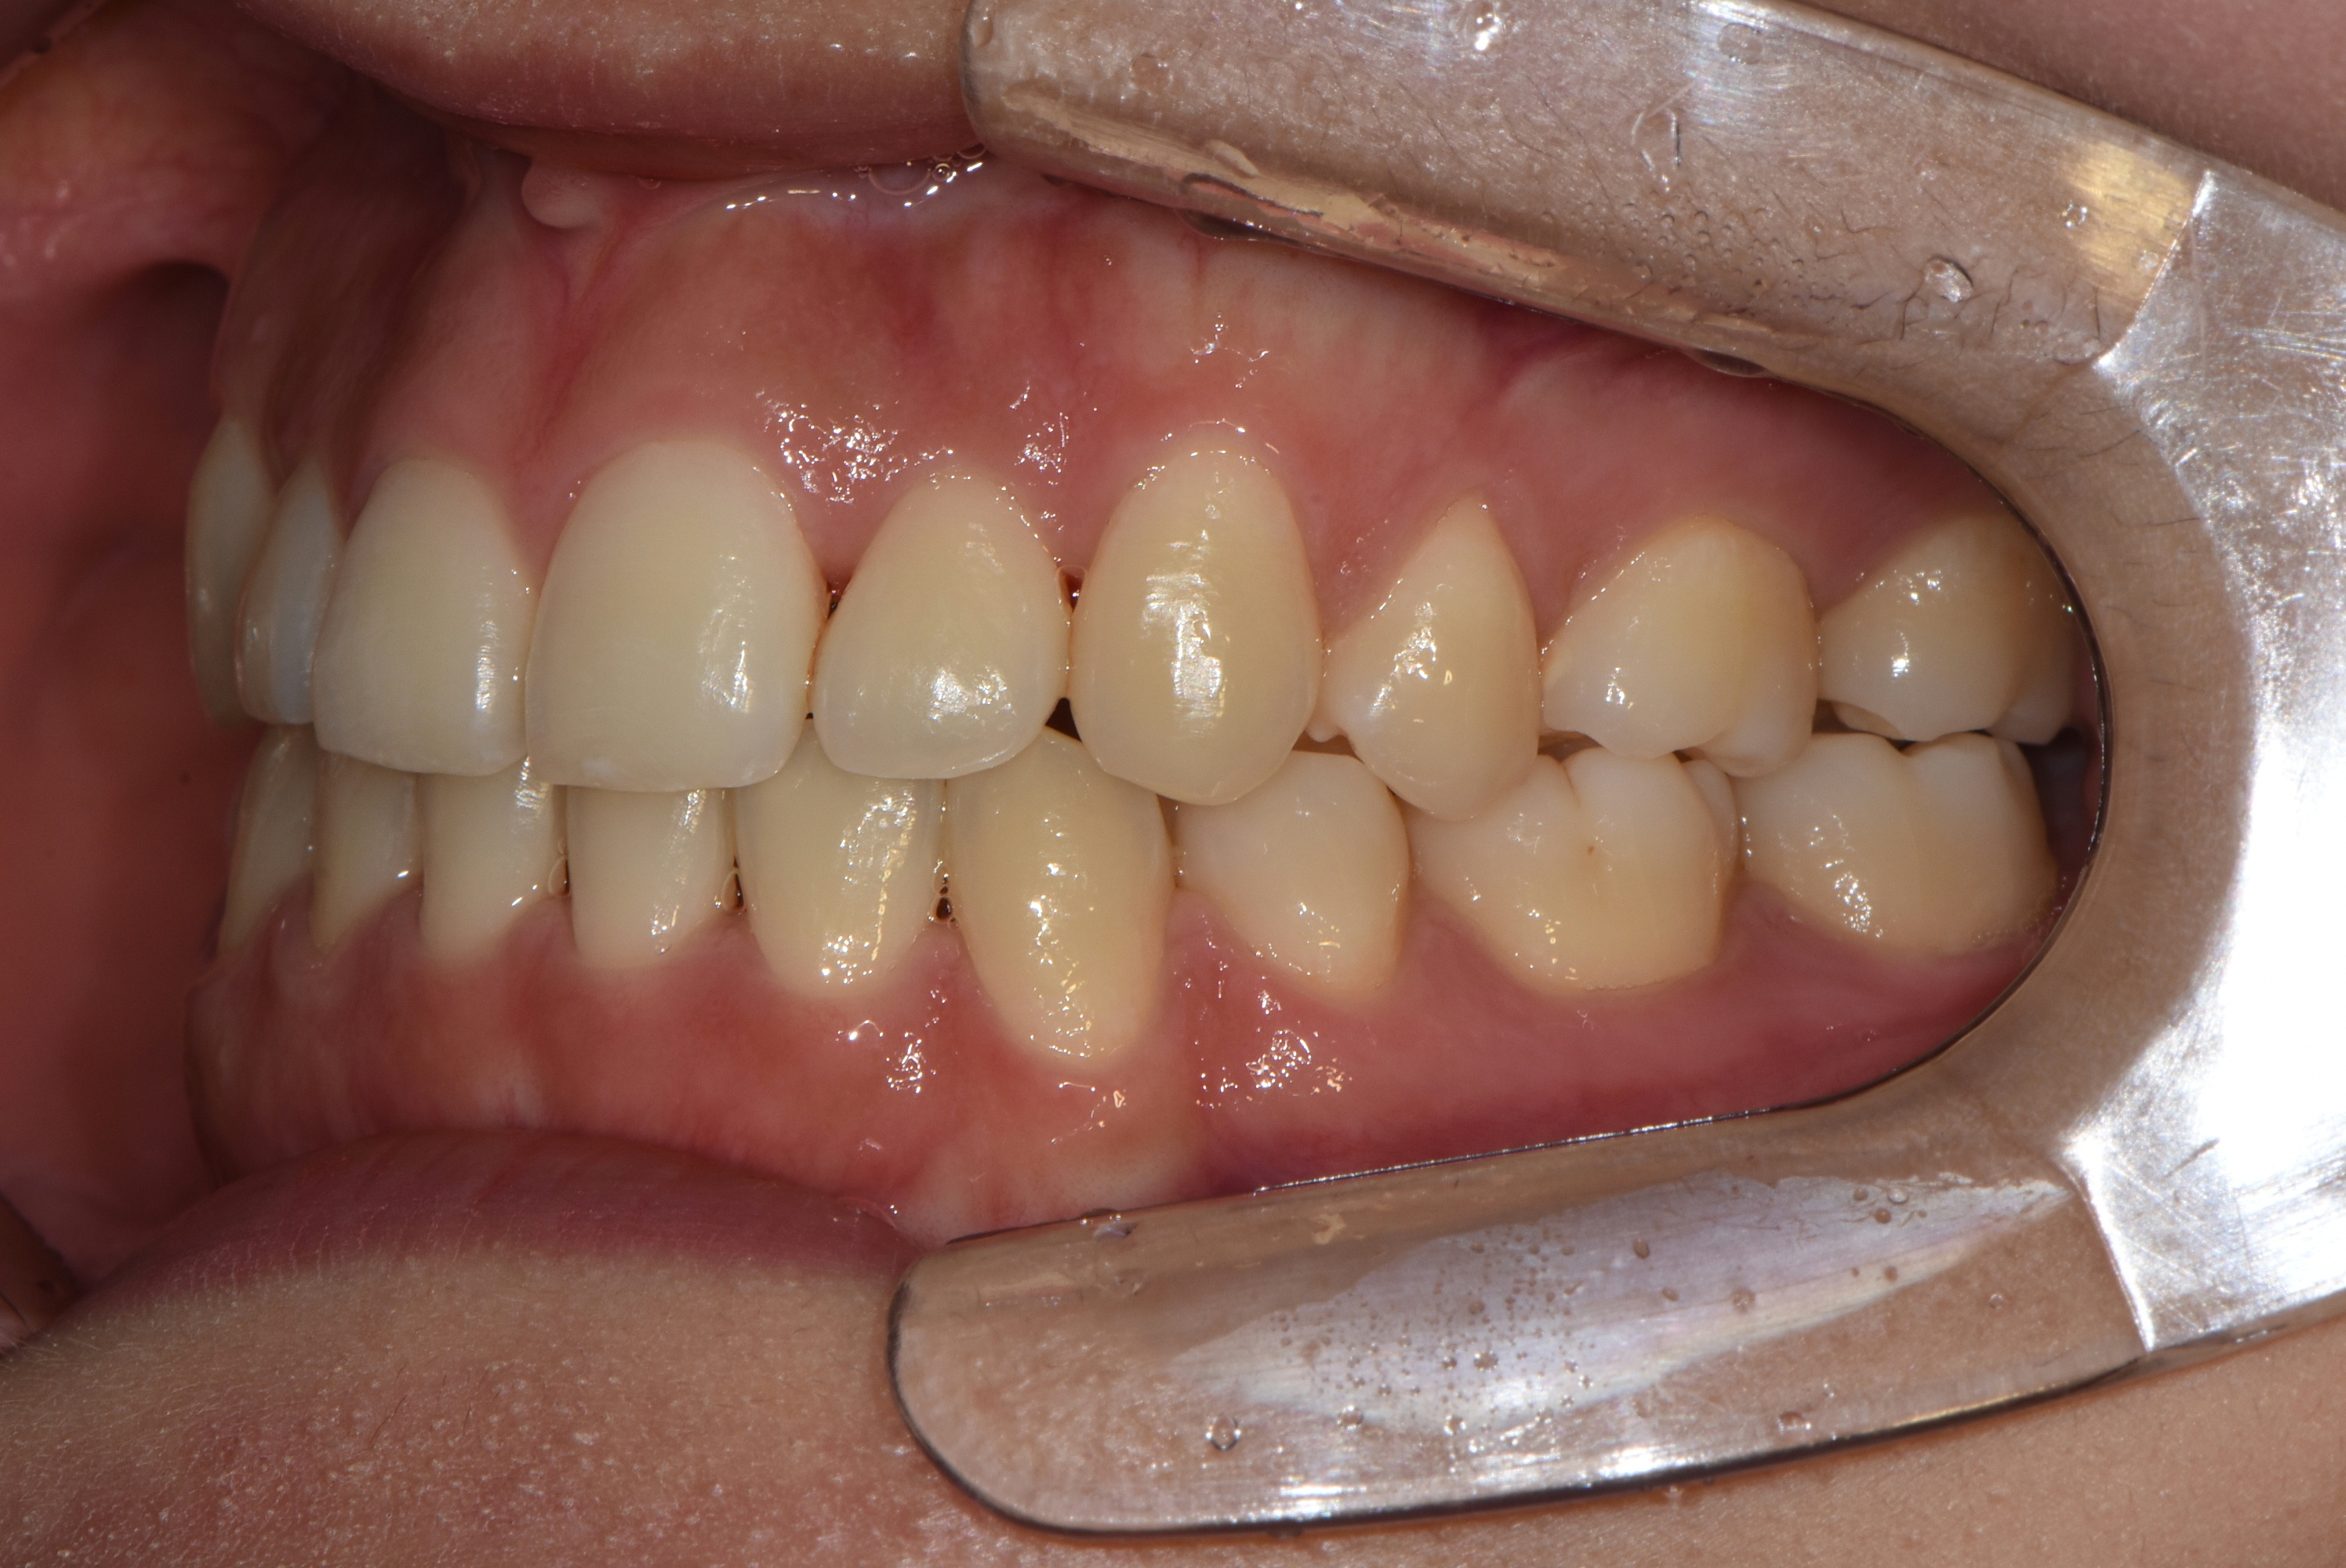

치료 후 사진입니다.